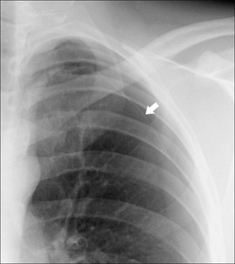

Figure 28.3 Chronic dyspnoea. Shadowing in the right lower zone. Apply Golden Rule 3—you only look for what you know. CXR conclusion—collapse of the right lower lobe.